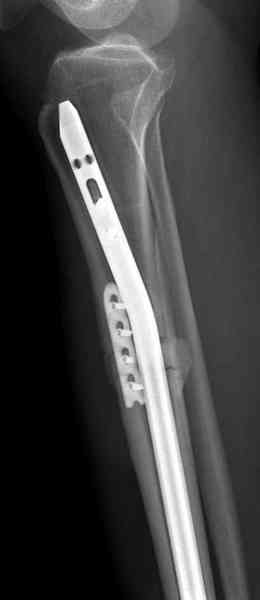

Недавно на нашей ежемесячной Morbidity&Mortality

conference мы разбирали похожий случай, ложный сустав большеберцовой кости после резекции опухоли.

К нашему онкологу-ортопеду обратился больной с жалобами на боли в голени, из рассказа - год назад была сделана биопсия большеберцовой кости, но название заболевания "не запомнил”.

Оперирован в военном госпитале с заменой сегмента

аллокостью большеберцовой кости и после демобилизации явился для постоянного наблюдения по месту жительства.

Наши имели проблему со сращением, пришлось им сделать динамизацию, дополнительную аутопластику.

Снимки представлены.